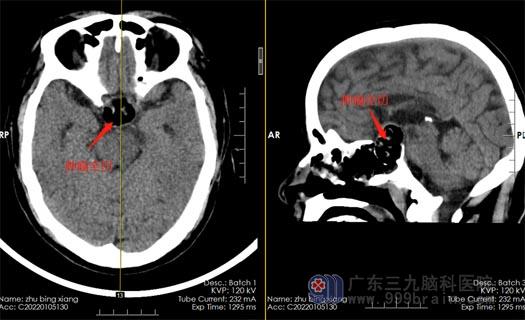

66岁的朱先生视力一向很好。3个月前,他突然发现自己的眼睛只能直直地看到眼前的东西,完全看不到两侧。朱先生到眼科就诊,医生告诉他眼睛没问题,建议去神经外科就诊。在广东三九脑科医院,经CT、核磁共振检查,证实是垂体瘤压迫视神经所致。

垂体瘤是较为常见的颅内肿瘤,垂体是颅内发生肿瘤最常见的部位。垂体的正上方为视神经、视交叉,与垂体相距约1厘米。早期垂体腺瘤常无视力视野障碍,如肿瘤长大,向上伸展,压迫视交叉,则出现视野缺损,以后病变增大,压迫较重,渐渐缺损可扩大至双颞侧偏盲。如果未及时治疗,视野缺损可再扩大,视力也会有减退,以致全盲。因为垂体瘤多为良性,初期病变可持续相当时间,待病情严重时,视力视野障碍可突然加剧,如果肿瘤偏于一侧,可致单眼偏盲或失明。

排除手术禁忌证后,神经外五科医疗团队为朱先生实施内镜经鼻蝶鞍区占位切除术,术中全切肿瘤,无脑脊液漏,出血仅100毫升,未输血,手术完成顺利。术后,朱先生恢复良好,他很满意手术效果,不仅避免了开颅,而且第二天即感觉视力和视野改善明显。